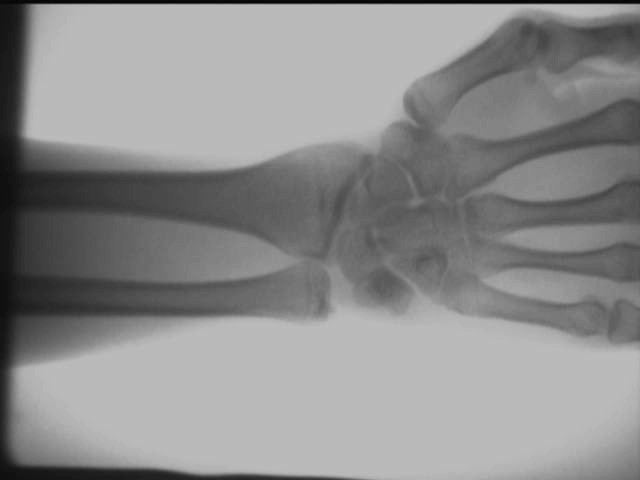

Armledseffekt

Ovanstående testresultat erhålls på plats med en AS-C200bärbar röntgenapparat